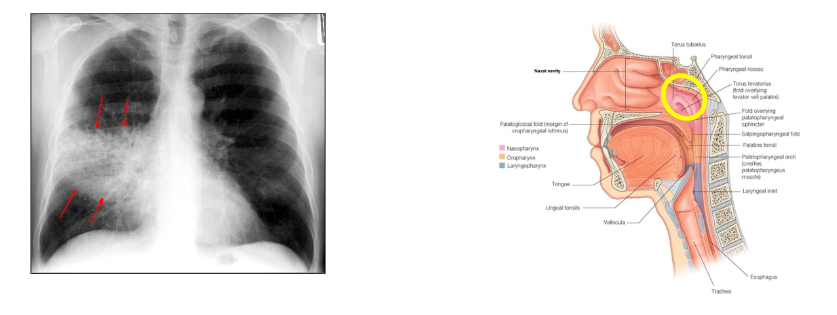

- Throat (pharyngitis or tonsilitis) -> abscess local extension (sinuses, mastoid)

Throat Infections caused by Strep A

- Strep A is commonest bacterial cause of pharyngitis/tonsilitis ("strep throat")

- Peritonsillar abscess (quinsy)

S. pneumoniae carriage

- Nasopharyngeal carriage of S. pneumoniae is necessary for transmisison of bacteira and precdes invasive disease